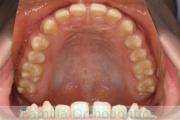

上の前歯の並びが気になるのできれいにしたい、ということで来院されました。マウスピース型矯正装置のひとつ、インビザライン/InvisalignR(薬機法および医薬品副作用被害救済制度の対象外)を用いて治療しました。

非抜歯で2年弱、20回程度の通院で治療が完了しました。

マウスピース矯正は、患者さんの協力に治療結果が左右されるところはリスクと言えるかもしれません。